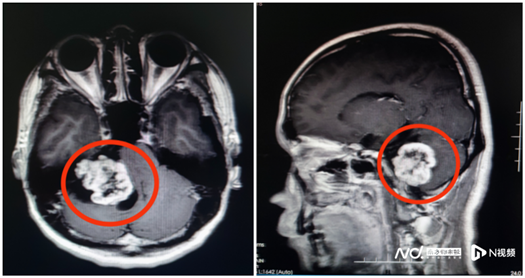

“从影像资料来看,怀疑是听神经瘤的可能性比较大。”该院副院长鲁明接诊时,发现一个鸡蛋大小的肿瘤正压着患者的内听道和脑干。除肢体乏力、面肌痉挛、头痛等症状外,还严重影响了他的听力。

完善术前准备,鲁明教授带领神经外五科团队为刘超行右侧桥小脑角占位性病变切除术,全切肿瘤。术后病理结果证实为听神经瘤。